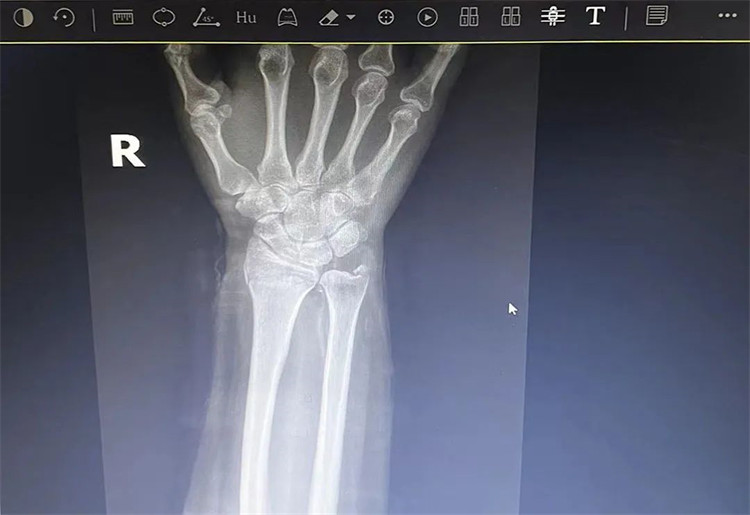

患者老年女性,50多歲,在騎電動車停下時因電動車倒下,右手著地,當即感覺,右腕及骶尾部腫痛伴右關節(jié)畸形、活動受限,急來我院就診。門診醫(yī)師結合病史、查體及輔助檢查后,診斷為:右橈尺骨遠端骨折、骶尾部挫傷并收入住院部。

患者入院后,中醫(yī)正骨科副主任鄭斌斌,認真查體及分析檢查結果后,考慮患者老年女性,建議患者采用拔伸牽引、端提、捺正等閉合手法復位后,行夾板固定,多能獲得較好療效。患者復位固定后,疼痛明顯減輕。避免了手術帶來的痛苦及手術開刀所需費用。